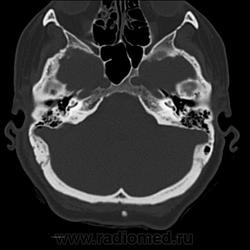

Да. Только это не аксиалы, а выровненные и несколько скошенные реконструкции для лучшего отображения линии перелома.

Известно место удара, есть линия перелома на своде. А воздух в черепе и шее заставил поковыряться